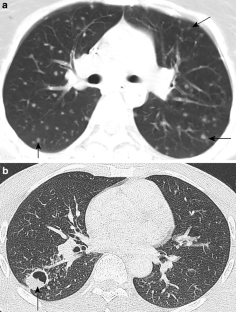

The CNS TB can be manifested (1) diffuse as tuberculous meningitis (TBM), (2) localized as tuberculoma or (3) tuberculous abscess or (4) in extradural and intradural spinal infections. Information on clinical presentation, underlying pathology and the distinguishing features is demonstrated. The TBM is further described, which may lead to cranial nerve palsy, hydrocephalus and infarction due to associated arteritis of the basal perforators. The differential diagnoses are vast and include other infections, such as bacterial, viral or fungal meningoencephalitis, malignant causes or systemic inflammation with CNS. Complicating factors of diagnosis and treatment are HIV coinfection, multi-drug resistance and TB-associated immune reconstitution inflammatory syndrome (IRIS).